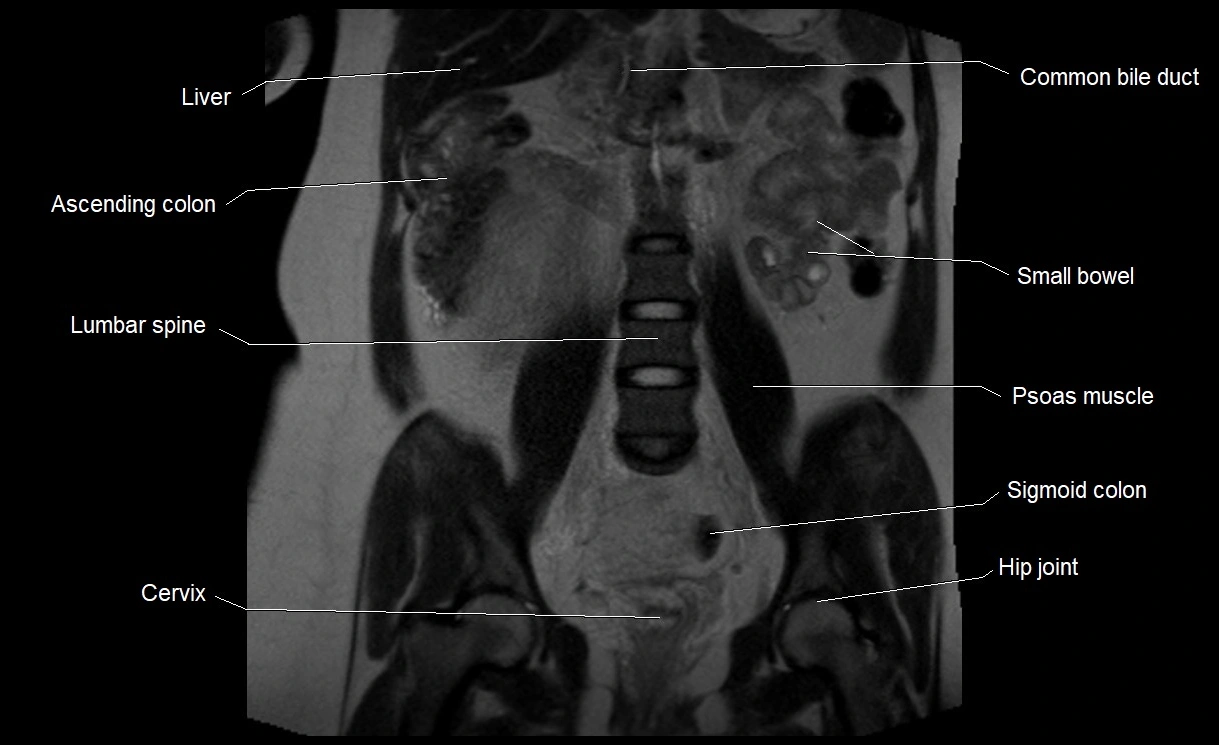

MRI Appearance

T2 HASTE (T2 GRE):

• Amniotic fluid shows very bright hyperintense signal

• Provides natural contrast against fetus and placenta

• Small particles (vernix) may appear as scattered hypointense foci within bright fluid

T1 GRE:

• Amniotic fluid shows low signal intensity (dark)

• Hemorrhage, infection, or proteinaceous content may cause focal or diffuse high signal intensity